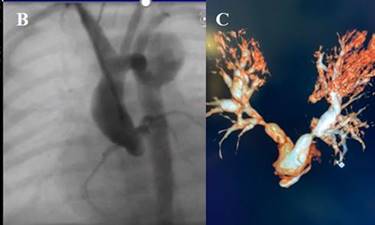

respiratoria mecánica y se administran prostaglandinas. El ecocardiograma Doppler color muestra estenosis aórtica crítica con

disfunción grave del ventrículo izquierdo (Figura 1A).

Fig. 1. Ecocardiograma Doppler

en donde se observa estenosis aórtica crítica (A). Angiografía desde acceso

carotideo post valvuloplastia aórtica (B).

Reconstrucción angiográfica de cerclaje quirúrgico de

ambas ramas pulmonares (C).

A las 18 horas de vida, se realiza

cateterismo cardíaco combinado y valvuloplastia

aórtica con balón híbrido (Tylsihak Mini, 6.0 ª 20

mm), mediante un acceso carotídeo derecho (disección)

(Figura 1B). Al cuarto día un ecocardiograma evidencia

gradiente transaórtico pico de 16 mmHg

con insuficiencia aórtica leve y comunicación interauricular amplia y ductus permeable.